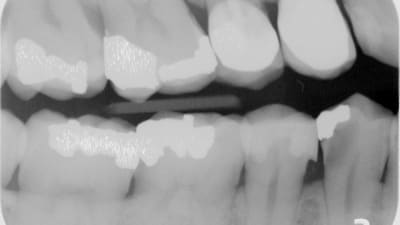

Clinical Briefs Restorative Direct Diagnosis and Treatment Planning Re-treating a Hyperemic Tooth With Deep Caries By Mark Malterud, DDS December 01, 2020 5 min read